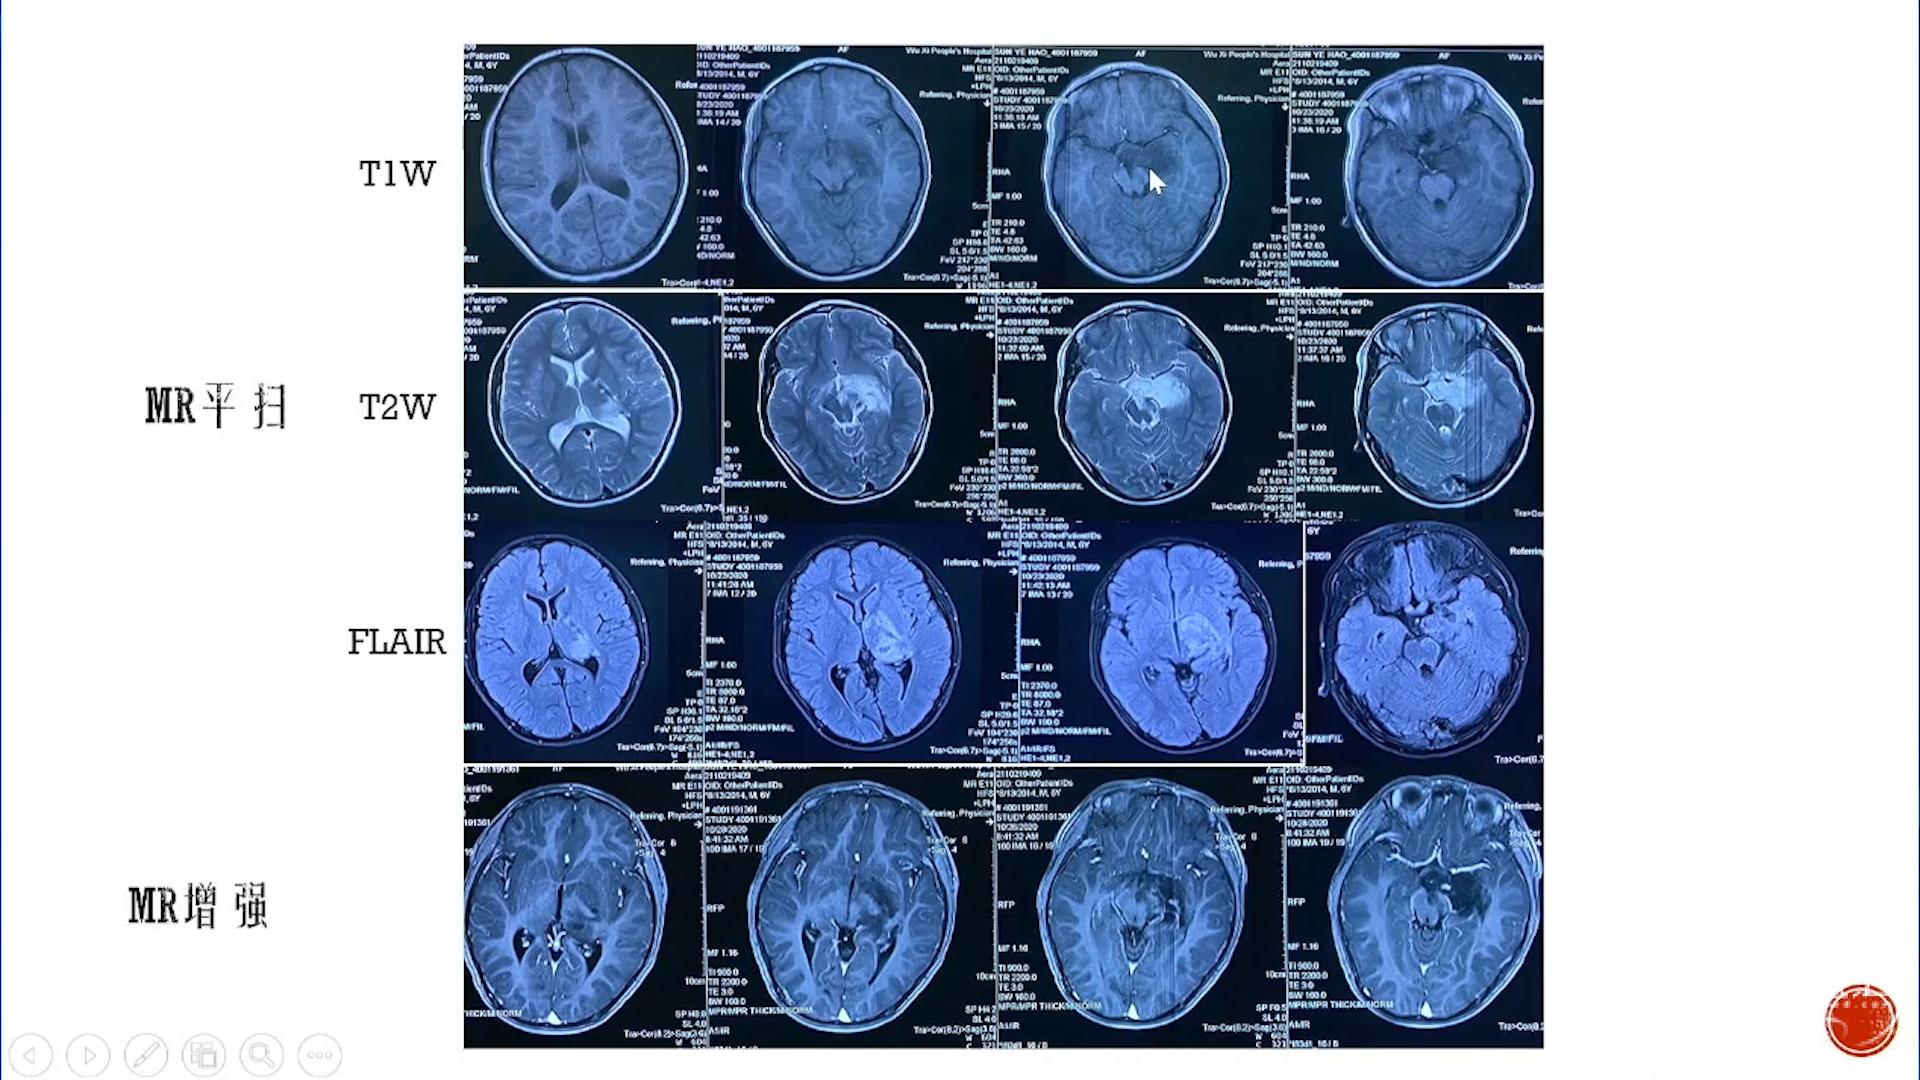

大脑半球儿童低级别胶质瘤

·致痫性肿瘤局限性肿瘤:节细胞胶质瘤、胚胎发育不良性神经上皮肿瘤(DNT)等

·弥漫性肿瘤